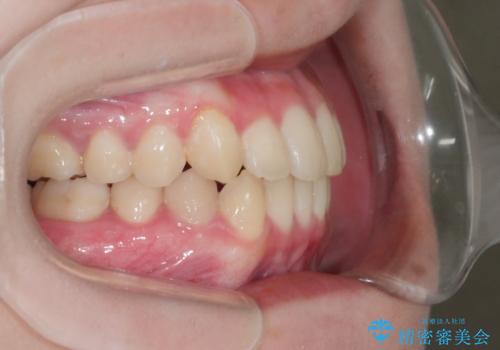

マイクロインプラントを使用して抜歯を回避!八重歯の非抜歯インビザライン治療

マイクロインプラントを使用することで非抜歯での治療が可能となりました。